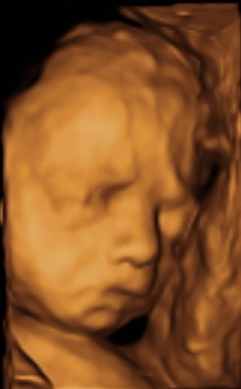

с дочкой все хорошо, кровоток замечательный, все измерили и посмотрели.. все хорошо. весит наша мадам 737 грамма (+/-50). по месячным у меня срок 25 недель и 4 дня.. по узи поставили на 3 дня меньше.. так что ПДР с 27.11 по 30.11 и вот фото нашей Алечки:

P.S. на сына на таких же фото совсем не похожа...))

фото мне тоже нравится, сравниваю с фото сына, дочка у нас серьёзная какая-то.. сын и в пузике улыбался и сейчас весельчак...ну совсем наши деточки большие уже там...